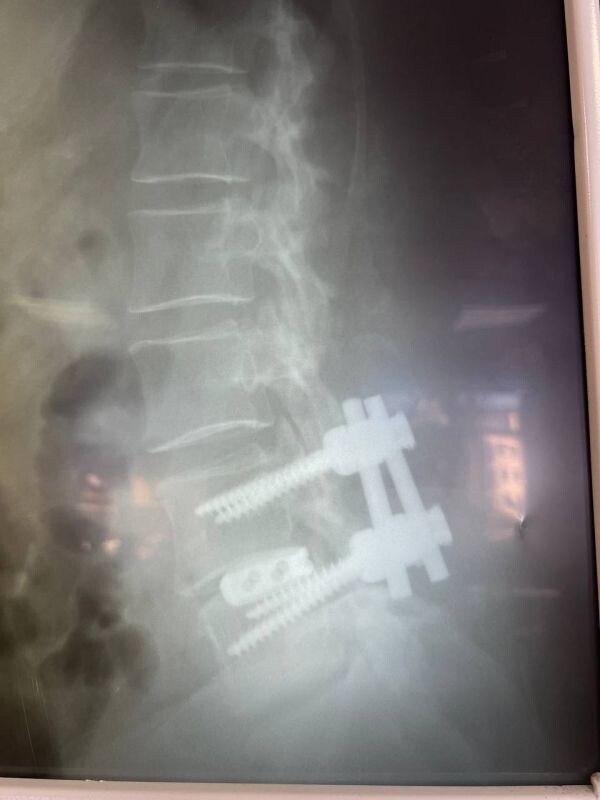

Фото: Минздрав Воронежской области

60-летняя женщина поступила в нейрохирургическое отделение. Её беспокоили боли в спине и ногах, онемение конечностей, затруднение ходьбы.

У пациентки выявили множество патологий, в том числе поражение межпозвоночных дисков, сужение пространства позвоночного канала.

В больнице № 11 врачи «разжали» позвонки с двух сторон, удалили грыжу и диски поражённых частей заменили на импланты.